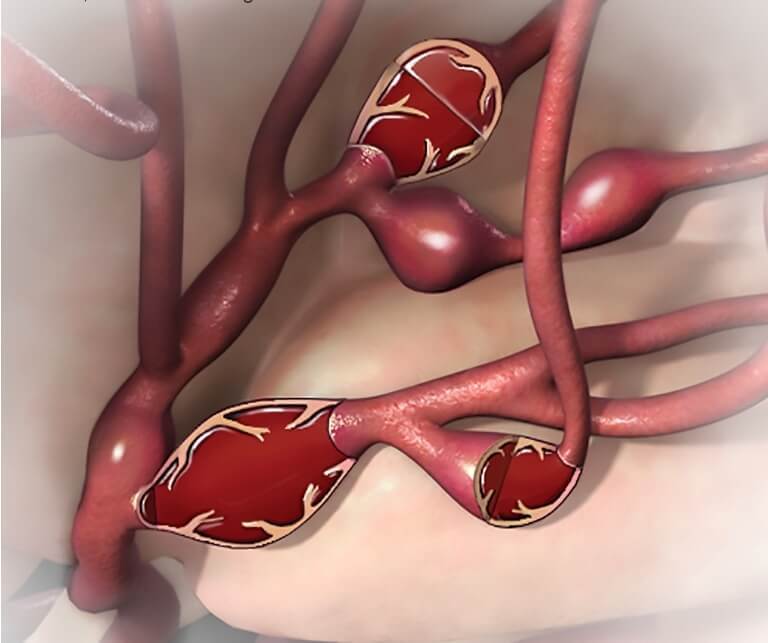

Снимки и иллюстрации микроаневризм сосудов головного мозга